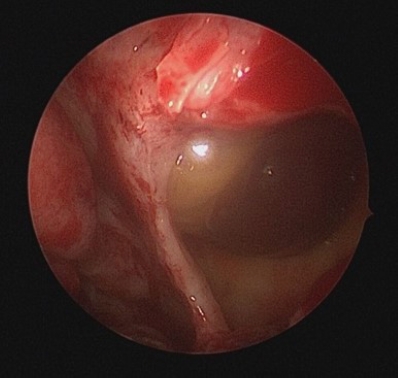

First, the medial orbital wall was repaired by the otorhinolaryngology team using an endoscopic transnasal approach with a navigation system (Fiagon Navigation System, Fiagon GmbH, Hennigsdorf, Germany). After uncinectomy and anterior ethmoidectomy, additional posterior ethmoidectomy was performed, followed by widening of the frontal and sphenoid ostia. This provided a clear surgical field for orbital compression and visualization of the left medial orbital wall fracture site (Fig. 2). The medial wall showed diffuse destruction with generalized herniation of the periorbita. After careful reduction of the herniated contents, a customized silastic sheet was inserted in an inverted U-shape (Fig. 3).

Endoscopic medial wall exposure Endoscopic view showing herniated periorbita at the medial wall defect.